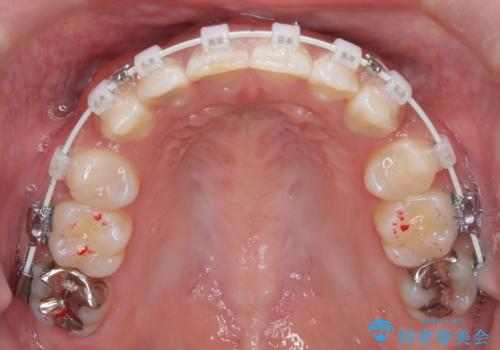

前歯の突出感を改善|上下4本の抜歯と審美ワイヤー矯正でバランスの取れた口元へ

- 患者様は、前歯の突出感を気にされて来院されました。診察の結果、歯列のスペースが不足しており、前歯を後方へ移動させるには抜歯が必要と判断。上下の小臼歯4本を抜歯し、目立ちにくい審美ワイヤー矯正(白いワイヤーと透明ブラケット)を使用して治療を行う計画を立てました。

抜歯によって前歯を下げるためのスペースを確保。その後、審美ワイヤー矯正を用いて、歯列全体のバランスを整えながら前歯を後方へ移動させました。治療後は、横顔のラインが整い、自然な口元になったことで、見た目も噛み合わせも改善しました。患者様からは「口元がすっきりして、自信を持って笑えるようになった」と喜びの声をいただきました。